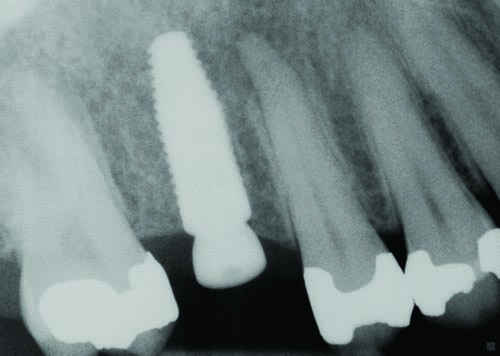

Fig. 32

Figs. 30–32: Two weeks later, the fourth appointment was reserved for restoration try-in and final impressions on the endosteal implants. It was during the fifth appointment, scheduled for two weeks later, that the implant-supported IPS E.max crown restorations were delivered, as well as the other definitive maxillary restorations, and any necessary adjustments made. These postoperative radiographs confirmed healing at the #3, #12 and #15 sites, which were all ultimately restored with Straumann implants, custom titanium abutments and IPS E.max crowns.